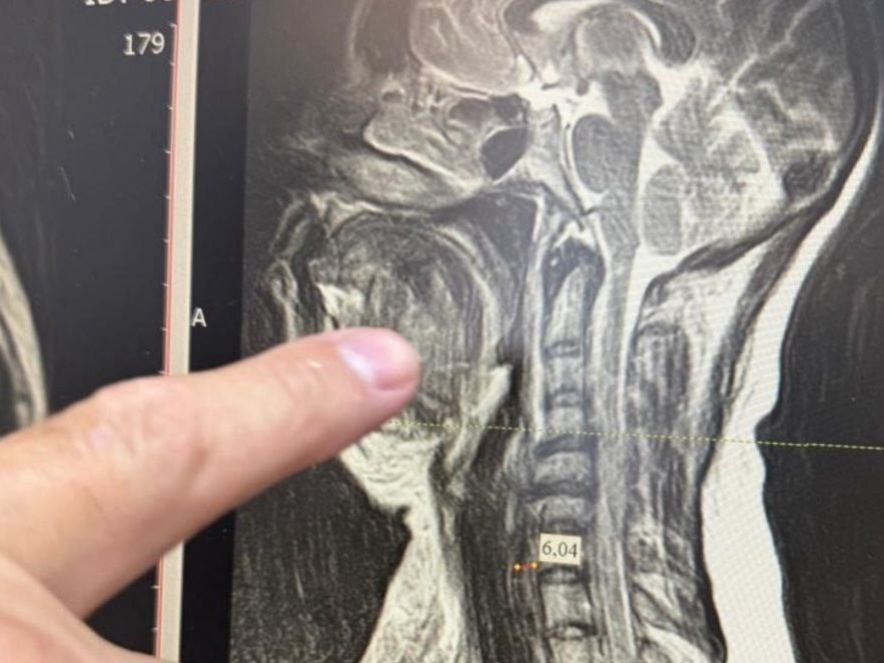

Медики столкнулись с одной из самых сложных форм осложнения – двусторонней флегмоной окологлоточного пространства, которая при отсутствии своевременного лечения в большинстве случаев заканчивается летальным исходом. Специалисты стали готовить женщину к экстренной операции. Из-за сильного отека тканей шеи невозможно было вставить трубку для дыхательного наркоза, поэтому работали через трахею.

Челюстно-лицевой хирург Шахбан Мисриев установил около восьми дренажей. Три дня пациентка провела в реанимационном отделении, подключенной к аппарату ИВЛ.